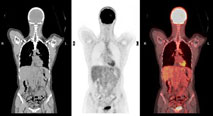

Her ses en PET-scanning af, hvordan sukkervand bliver optaget i musklerne. Scanneren fremstiller sort-hvid-billeder, og derefter bliver de behandlet og farvelagt i et computerprogram.